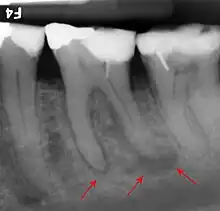

Bone loss in periapical radiograph

The 2018 Disease Classification of Periodontal Diseases and Conditions breaks down the category of periodontitis into three forms and each of these forms are further broken down into two or more subcategories.[7]